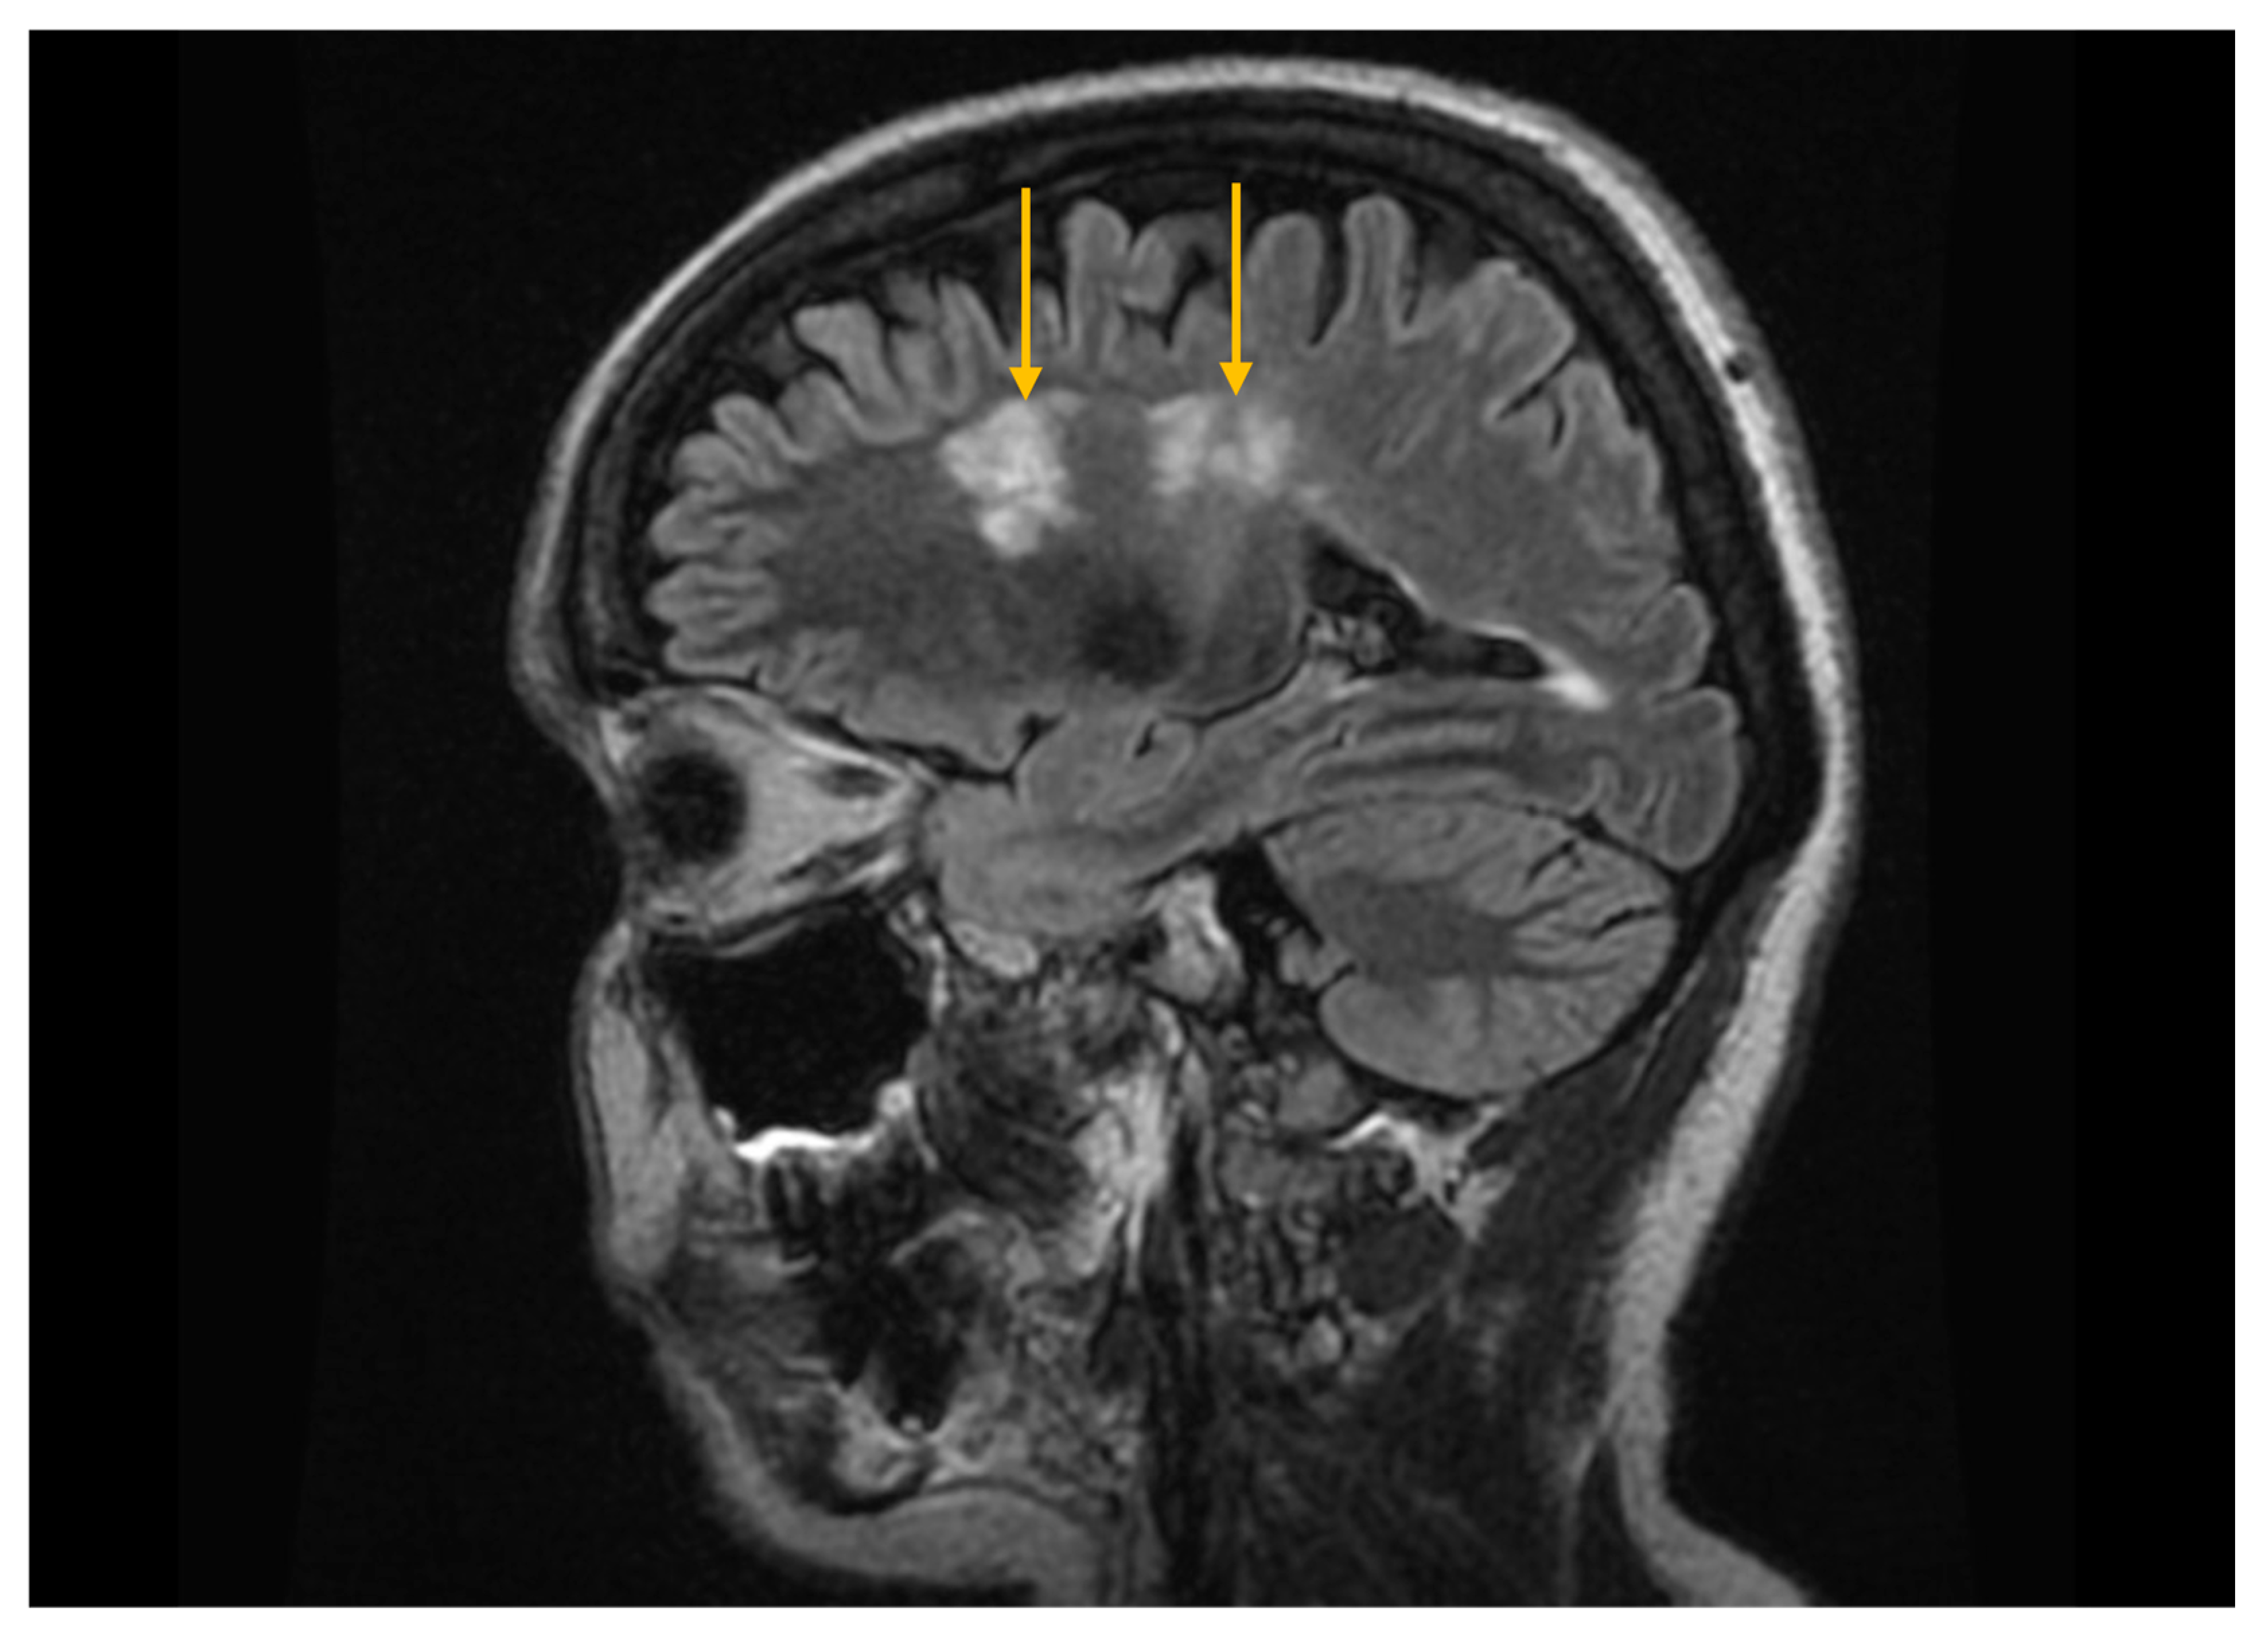

In patients with Sjögren’s syndrome and neurological involvement, MRI may reveal cerebral demyelinating lesions with a distribution and appearance similar to those observed in multiple sclerosis (Figure 6) [25]. However, the published data regarding their significance are contradictory; some studies report a higher prevalence of demyelinating changes in Sjögren’s syndrome compared with control groups, while others do not demonstrate significant differences, suggesting that these lesions may instead reflect changes associated with normal physiological aging [53,54].

Figure 6. Magnetic resonance imaging (MRI) of the brain using the fluid-attenuated inversion recovery (FLAIR) sequence. Sagittal FLAIR MRI image demonstrates hyperintense cerebral demyelinating lesions (arrows), with a distribution pattern similar to that seen in multiple sclerosis.